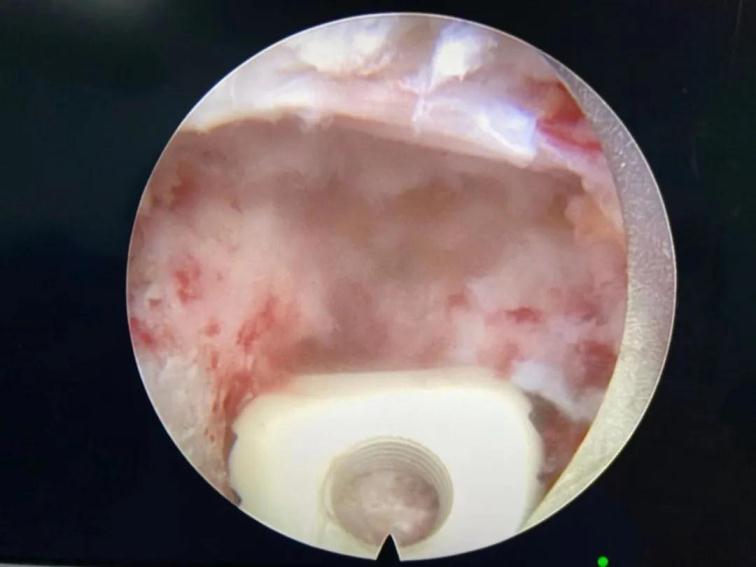

鏡下椎間融合